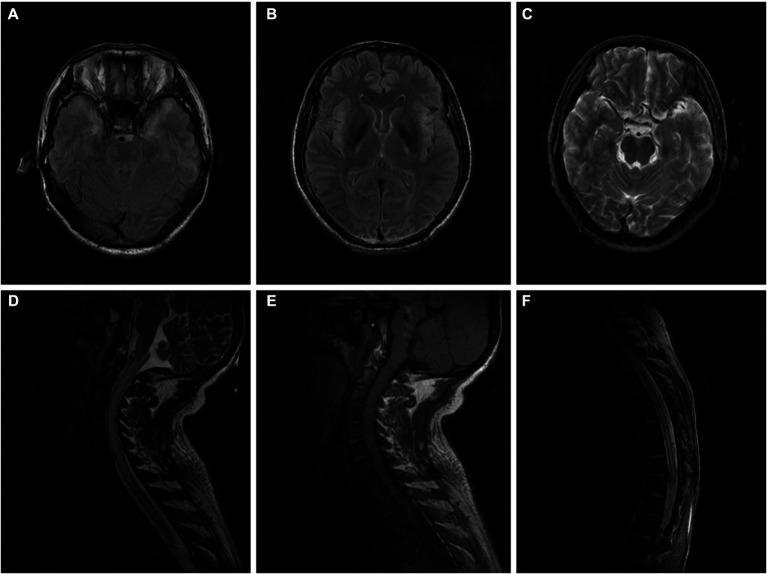

Xylene has the potential to cause nervous system disturbances since it is a lipophilic substance with high affinity for lipid-rich tissue, such as the brain. Involvement in the spinal cord, especially long segmental spinal cord lesions that permeate almost the entire cervical and thoracic spinal cord, is extremely rare. We report two cases of occupational exposure to excessive xylene, both of which presented with severe and rapidly progressive numbness and weakness in the limbs that, more importantly, led to poor outcomes: one died and the other was left severely disabled. In both, spinal magnetic resonance imaging showed long segmental lesions in the cervicothoracic spinal cord. These findings may provide some insights into the effects of xylene as an isolated agent on the spinal cord injury.